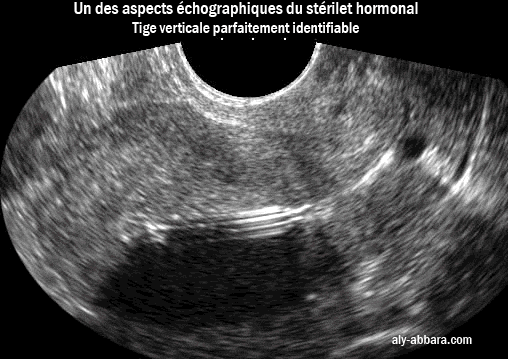

Stérilet hormonal : un de ses aspects échographique : tige verticale parfaitement identifiable

Il s'agit d'un des aspects de la tige verticale du stérilet hormonal (au lévonorgestrel) avec la formation d'un cône d'ombre

par la réflexion des ondes ultrasons au niveau de cette tige qui est parfaitement individualisable.

Le cône d'ombre ne se voit pas toujours avec ce type de DIU (voir cette image)

La tige verticale du stérilet hormonal n'est pas toujours identifiable (voir cette image)